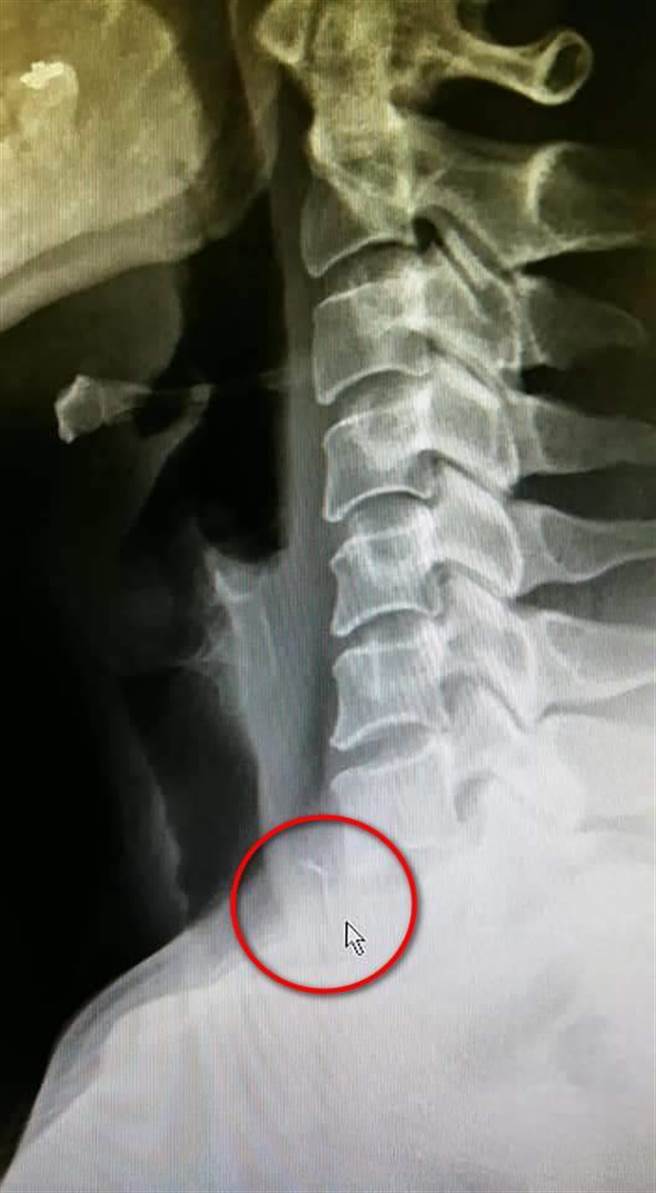

花莲一名70多岁的陈姓老翁日前深夜因喉咙疼痛,被家人送往花莲慈济医院就医,透过电脑断层检查发现他食道中有鱼刺,经耳鼻喉科副主任周昱甫紧急进行食道镜手术,取出2公分大的鱼刺,顺利解除鱼刺卡喉危机。

周昱甫说,民眾因鱼刺卡喉就医时,耳鼻喉科会先使用耳鼻喉科镜检查,再使用内视镜找鱼刺,找不到时则进一步使用X光或电脑断层做详细检查。